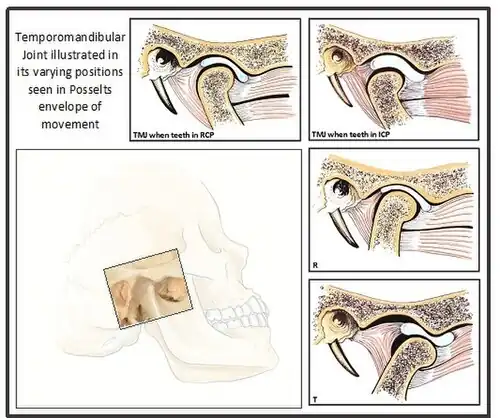

The TMJ is formed from the temporal bone of the cranium, specifically the glenoid fossa and articular tubercle and the condyle of the mandible, with a fibrocartilaginous disc lying in between. It is classified as a ginglymoarthrodial joint[5] and can perform a range of gliding and hinge type movements. The disc, which lies in between is composed of dense fibrous tissue and is predominantly avascular and lacking nerves.[2]

Centric relation (CR) describes a reproducible jaw relationship (between the mandible and maxilla) and is independent of tooth contact. This is the position in which the mandibular condyles are located in the fossae in an antero-superior position against the posterior slope of the articular eminence.[12] It is said that in CR, the muscles are in their most relaxed and least stressed state. This position is not influenced by muscle memory, but rather by the ligament which suspend the condyles within the fossa. Therefore it is the position that dentists use to create new occlusal relationships as for example, while making maxillary and mandibular complete dentures.

When the mandible is in this retruded position, it opens and closes on an arc of curvature around an imaginary axis drawn through the centre of the head of both condyles. This imaginary axis is termed the terminal hinge axis. The first tooth contact that occurs when the mandible closes in the terminal hinge axis position, is termed Retruded Contact Position (RCP).[13] RCP can be reproduced within 0.08mm of accuracy due to the non-elastic TMJ capsule and restriction by the capsular ligaments, thus it can be considered a ‘border movement’ in Posselt’s envelope.[14]

Posselt's Envelope of Border Movements

Posselt’s Envelope of Border Movement (often referred to as the 'border movements of the mandible') is a schematic diagram of the maximum jaw movement in three planes (sagittal, horizontal and frontal). This encompasses all movements away from RCP, and includes: